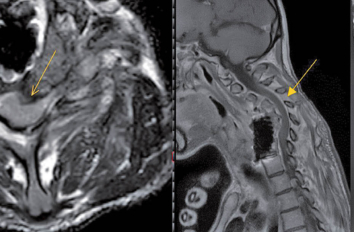

Spondylodiszitis der Halswirbelsäule

Anhand des Fallberichtes einer Spondylodiszitis der Halswirbelsäule werden im folgenden Artikel die klinische Bedeutung dieses Krankheitsbildes, die zweckmässigen…